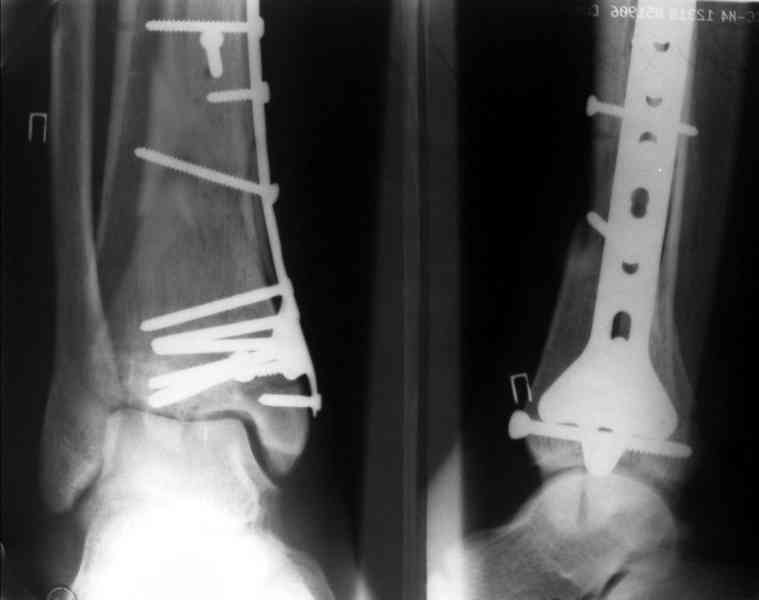

Послала ещё два снимка, если не пройдут, пошлю ещё. Дрягин. Если есть вопросы, готов ответить.